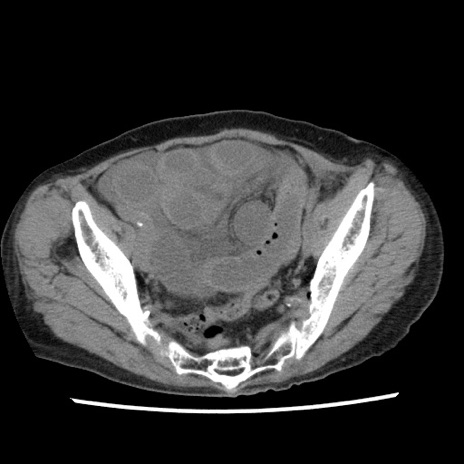

症例1(横断像)

【症例】80歳代女性

【主訴】腹痛

【現病歴】8時間前から腹痛あり来院。

【既往歴】糖尿病、脂質異常症、子宮体癌にて子宮全摘術

【身体所見】意識清明・会話良好だが腹痛で苦悶様、全腹部にわたって反跳痛と圧痛あり

【データ】WBC 13600、CRP 0.14、LDH 224、CK 90